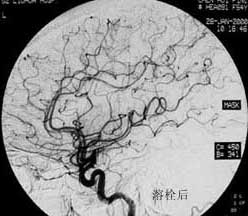

二、脑动静脉畸形(AVM)

---- Spetzler对AVM的分级方法已越来越多地被人们接纳和采用。脑AVM最危险的症状之一是出血。AVM每年的出血率为 3%~4%,第一年内再出血约6%。每次出血的致残率为30%,病死率为12.5%,而积极治疗的总残废率加病死率在10%以下。

---- 血管内栓塞对于单支或少数供血动脉的AVM,特别是新近出血的病例,可以达到微侵袭、痛苦小、疗效迅速的目的。 近来改变栓塞方式,将导管直接放置 畸形血管团内,注射NBCA胶,可使畸形团的解剖 治愈率提高至27%。再加上更细、超 滑的微导管问世,栓塞的并发症更为降低。针对大型、功能区 的AVM栓 塞可缩小其体积,改善血液动力学分布,以利于显 微外科技术切除或放射外科治疗,是后二者的重要辅助手段。

----立体定向放疗(γ-刀、χ-刀)对AVM是一种有希望的选择性治疗方法。据文献报道,AVM治疗后年消失率30%~50%,2年 消失率70%~90%,其消失速度与所用的照射量成正比,与AVM 的大小成反比。从治疗到AVM完全闭合之前每年的出血率 3%~4%,与自然出血史相同,所以对有出血史的患者,应优先采用栓塞或手术方法。大型AVM经若干次栓塞后体积缩小即可 放射治疗。但栓塞物质应是NBCA。其它颗粒或丝线栓塞,均有复发之虞。栓塞加立体定向放疗可使60%~80%的患者免于开颅 手术而获治愈。